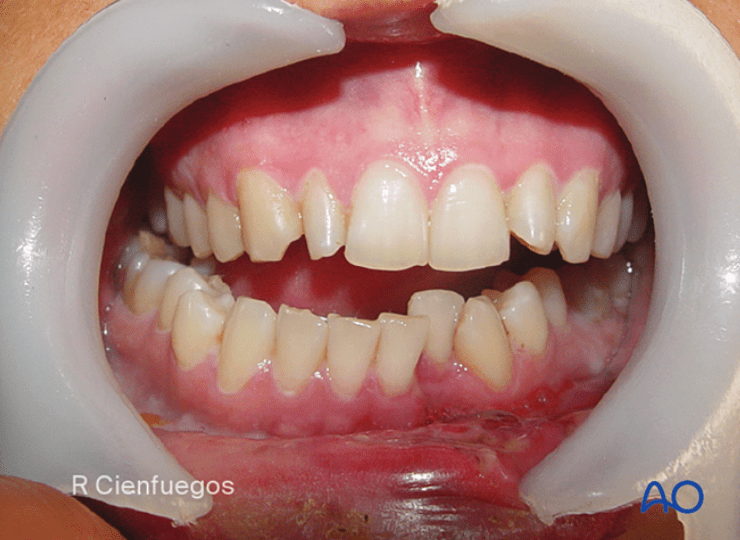

47M presents with multiple facial injuries following high impact car accident where he slammed the side of his chin/face into steering wheel. Endorses malocclusion. CT max face shows medial displacement of condyle.

Where does he most likely have fractures? In what order should they be repaired and how?

R condylar neck fx and L mandibular body or parasymphysis fx

First, you place pt in pre-morbid occlusion with arch bars and MMF. Then, you repair fx's within dental arch, moving anterior to posterior to guarantee proper occlusion. At the end, you reduce edentulous fractures (ie. condyle)

Can use 1 monocortical mini plate (2.0mm) per fracture making sure to have 3 holes on each side.

**studies no longer support needing rigid fixation of one of the fractures (with 2 mini plates, locking plate or 2.0 recon plate) - https://pubmed.ncbi.nlm.nih.gov/37772893/

Then you can treat the condylar neck fracture with MMF for 2 weeks or fixate it with 1-2x 2.0mm miniplates depending on height of fx.